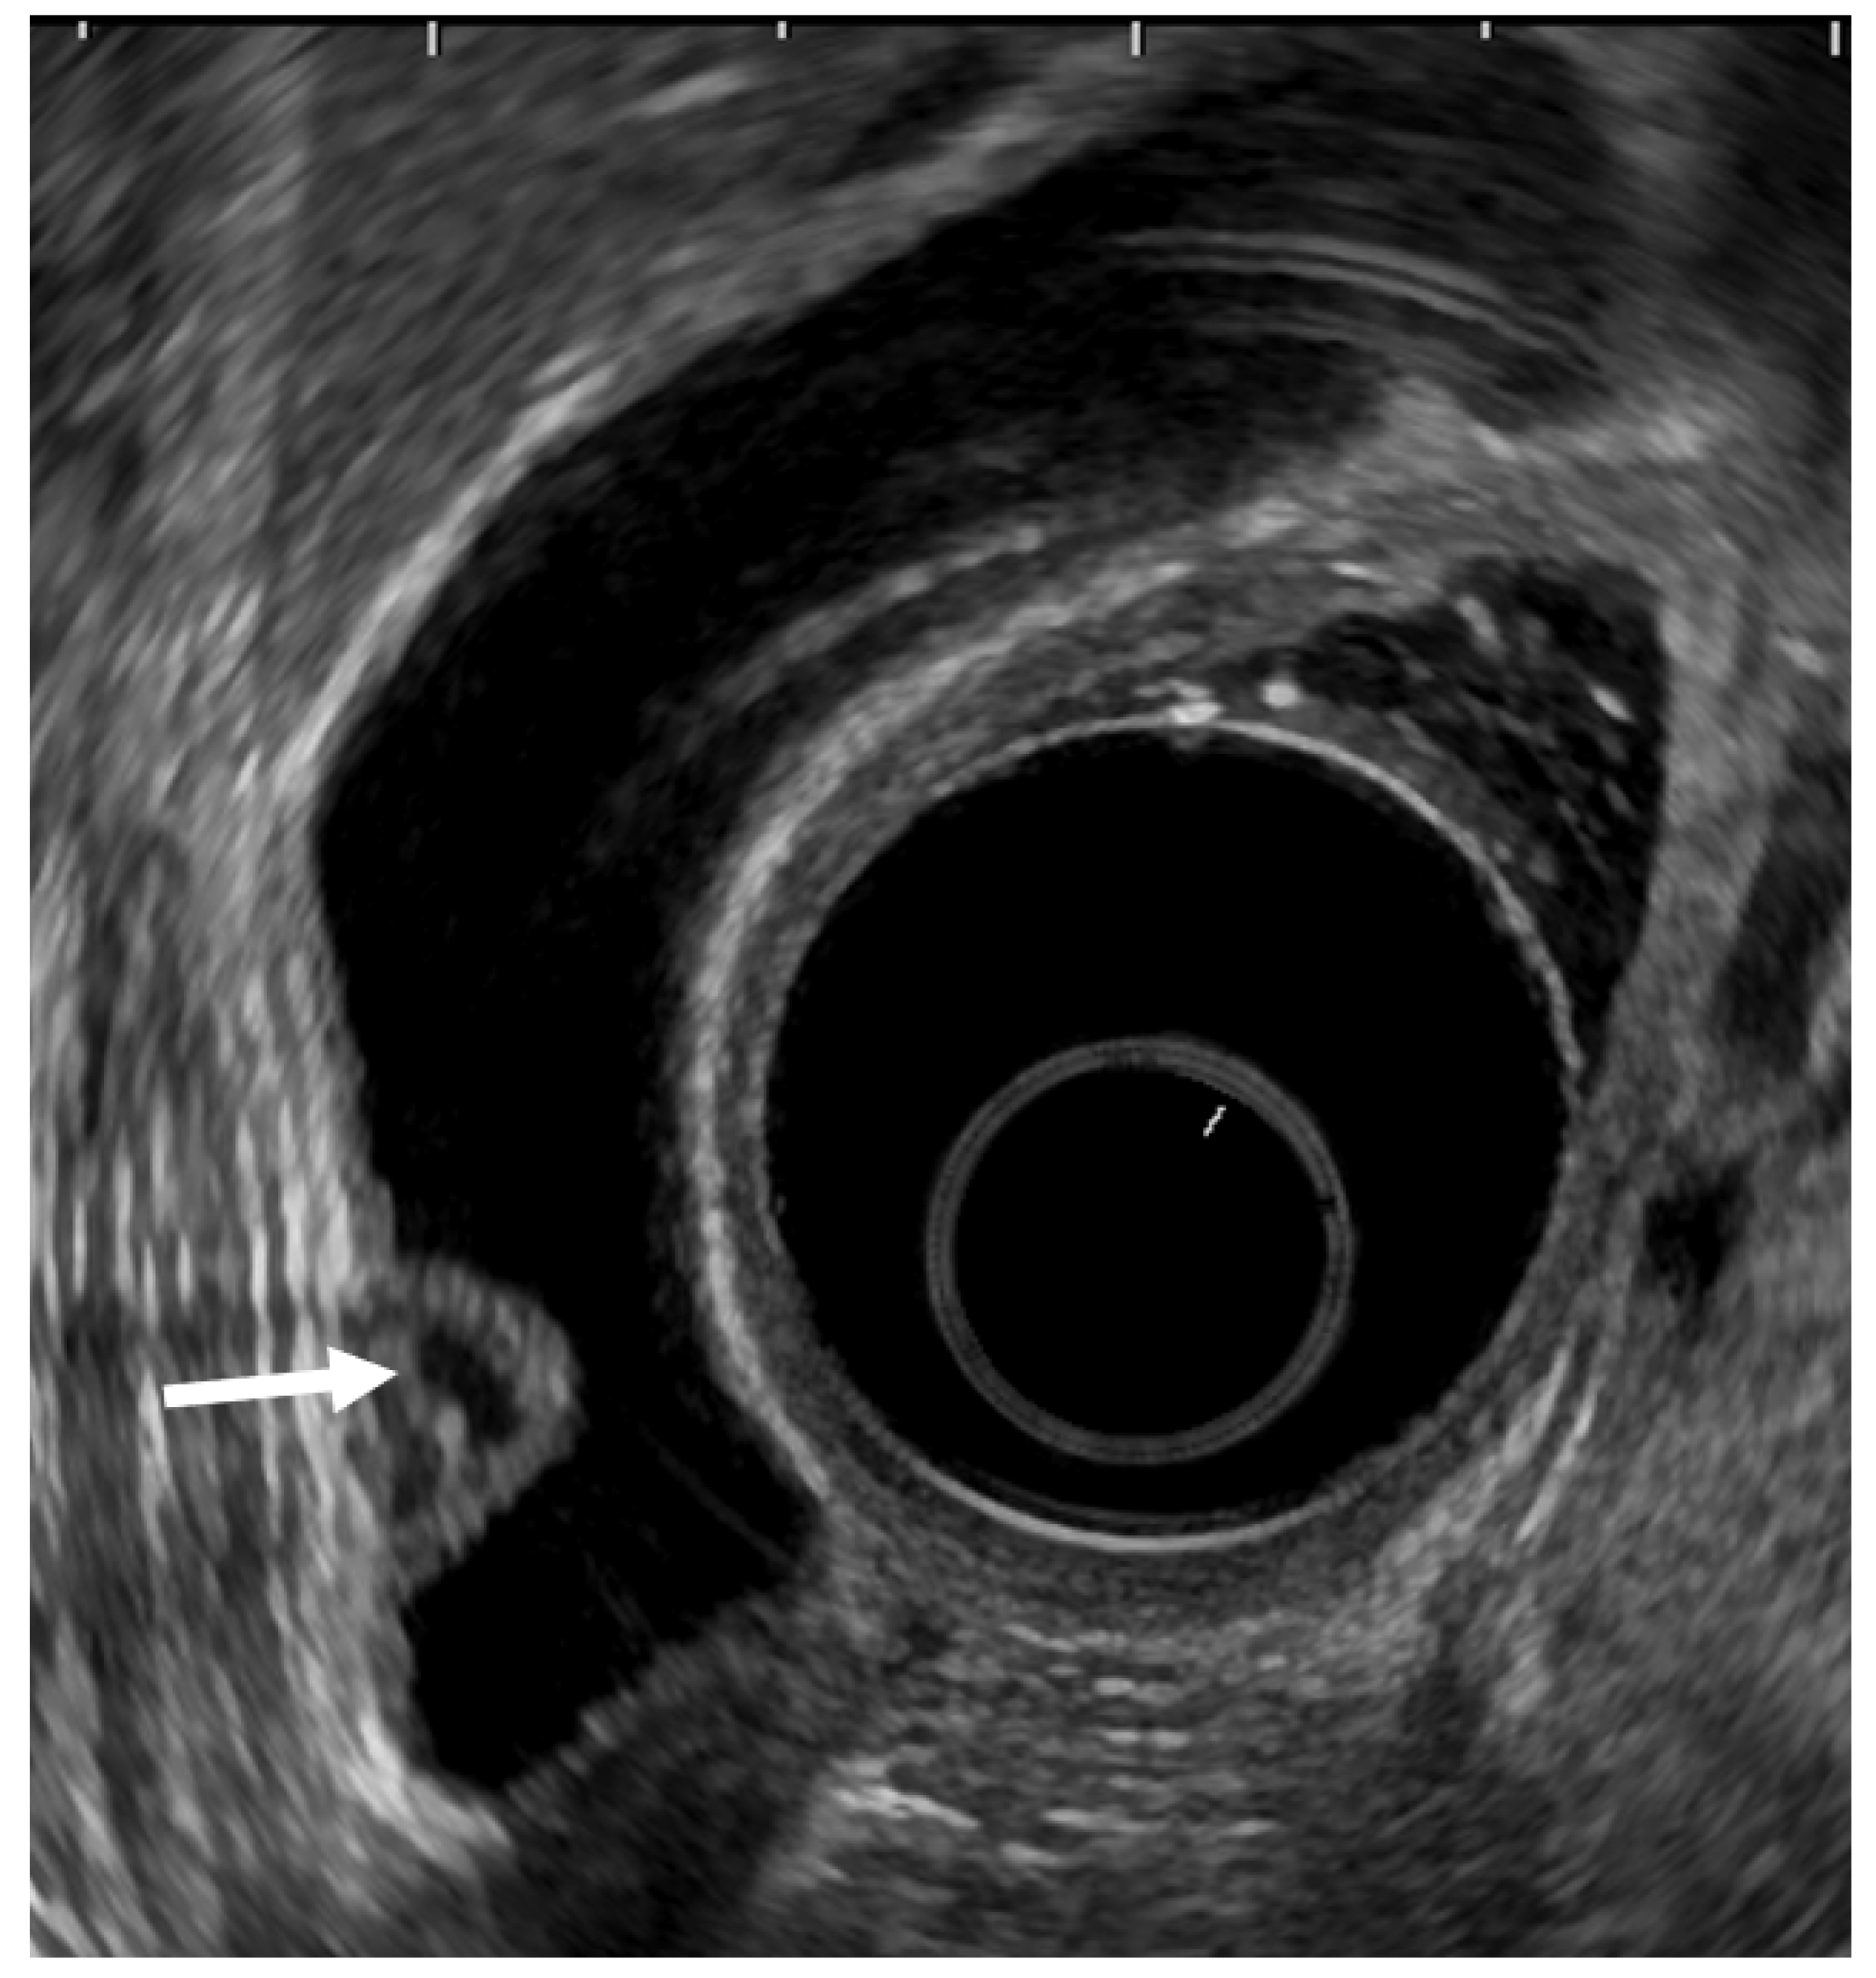

EUS can visualize localized ADM as a sessile polypoid lesion with small cystic areas corresponding to the proliferation of Rokitansky–Aschoff sinuses (RAS; Figure 3) [27]. Comet tail artifacts are also occasionally observed owing to multipath reflection from RAS or intramural calculi. Several cases of GB carcinoma concomitant with ADM have been recently reported [35,36,37,38,39]. Therefore, the possibility of concomitant GB carcinoma with ADM in sessile lesions with multiple microcysts should be kept in mind.

Figure 3.

EUS image ADM (localized type). EUS shows localized ADM as a sessile polypoid lesion with anechoic areas (arrow) corresponding to RAS proliferation. The surface is relatively smooth.